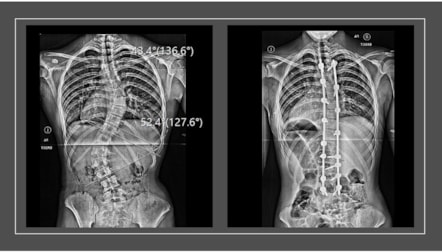

Phoebe was just 15 when she was diagnosed with scoliosis – a sideways curvature of the spine most found in adolescents.

Unfortunately, the brace wasn’t enough to slow the progression of the curve, which threatened to compress her organs and reduce her lung capacity.

Just two weeks after completing her GCSEs, Phoebe underwent a six-hour spinal fusion surgery at Evelina London Children’s Hospital, part of Guy’s and St Thomas’ NHS Foundation Trust.

Surgeons fused her spine from the T4 to L4 vertebrae – essentially from just below her collarbones to her lower back – using titanium rods to stabilise her spine.

The surgery left her unable to bend her spine and only able to hinge at the hips – but it also made her two inches taller.